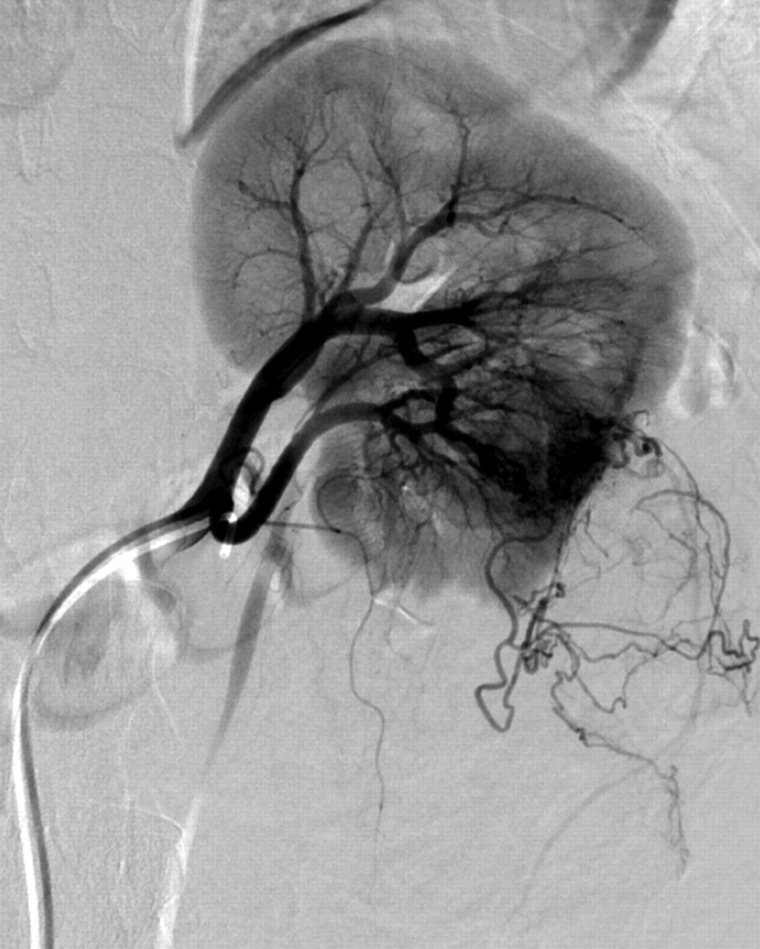

我们报告一位36岁的白人妇女,她以计算机断层扫描诊断为创伤后腹膜后出血而来到急诊室。患者临床稳定后,进行选择性动脉栓塞。血管平滑肌脂肪瘤的供血动脉用8毫米Amplatzer II型血管塞成功治疗。左肾上极由独立的肾上动脉供应,保存完好。结果,肾血管平滑肌脂肪瘤坏死,手术切除整个肾血管平滑肌脂肪瘤。本病例说明了一种简单有效的应用Amplatzer血管堵塞器进行血管栓塞,而无需额外缠绕。

We report on a 36-year-old Caucasian woman who presented to the emergency department with post-traumatic retroperitoneal bleeding diagnosed by computed tomography. After clinical stabilization of the patient, selective arterial embolization was performed. The angiomyolipoma's feeding artery was successfully treated with an 8-mm Amplatzer Vascular Plug Type II. The upper pole of the left kidney, which was supplied by a separate upper renal artery, was conserved. Consequently, the renal angiomyolipoma became necrotic and surgical resection of the entire renal angiomyolipoma was performed. This case illustrates a simple and effective application of an Amplatzer Vascular Plug occluder for vessel embolization, without additional coiling.